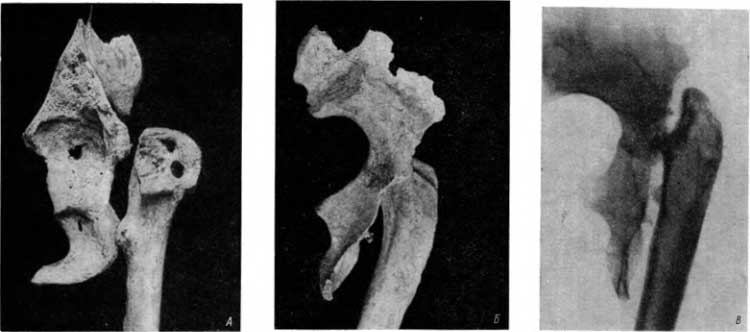

Следующая находка иллюстрирует картину, казалось бы, полного излечения путем образования костного блока. Это скелет пожилого мужчины из погребения эпохи поздней бронзы — культура скорченных костяков, тысяча лет до нашей эры (из материалов Манычской экспедиции ГАИМК, 1933 г., раскопки М. И. Артамонова).

Тела XI и XII грудных позвонков и I и II поясничных позвонков слиты в одну массу, имеется двусторонний анкилоз мелких суставов верхних трех позвонков, частичное окостенение желтых связок между XI и XII грудными позвонками и межостистых связок в той же области. Угловой кифоз в переходном пояснично-грудном отделе объясняется главным образом частичной деструкцией передней части тел XII грудного и I поясничного позвонков. Тела слившихся позвонков как бы «облиты сахаром» в силу окостенения передней продольной связки на всем протяжении этого отдела (рис. 25, А).

Рис. 25. А — туберкулезный спондилит с образованием костного блока из четырех позвонков, в свищевой ход введена спичка; Б — отсутствие спокойной стабилизировавшейся костной структуры между анкилозированными телами XII грудного и I поясничного позвонков, в XII грудном позвонке участок деструкции.

Туберкулезный процесс как будто бы излечен. Все же на рентгенограмме в области анкилоза, между телами XII грудного и I поясничного позвонков, прослеживается отчетливый склероз (рис. 25, Б). Следовательно, нет спокойной структуры; полное выздоровление не наступило.

Кроме того, тщательный осмотр костного препарата обнаруживает наличие свищевого хода, а на боковой рентгенограмме в теле XII грудного позвонка, на границе задней и средней трети, определяется участок деструкции. Таким образом, процесс не может быть рассмотрен как уже совершенно законченный.

Между тем такие картины в практической деятельности рентгенолог обычно рассматривает как вполне излеченные туберкулезные спондилиты. На это явление обратил внимание также Шморль. Он описал случай, трактовавшийся на основании клинических и рентгенологических данных в течение многих лет как излеченный туберкулезный спондилит с образованием костного блока между III и IV поясничными позвонками. Между тем на секции Шморль на распиле позвоночника обнаружил 2 полости с казеозными массами.[71] Конечно, теперь помогает томография.